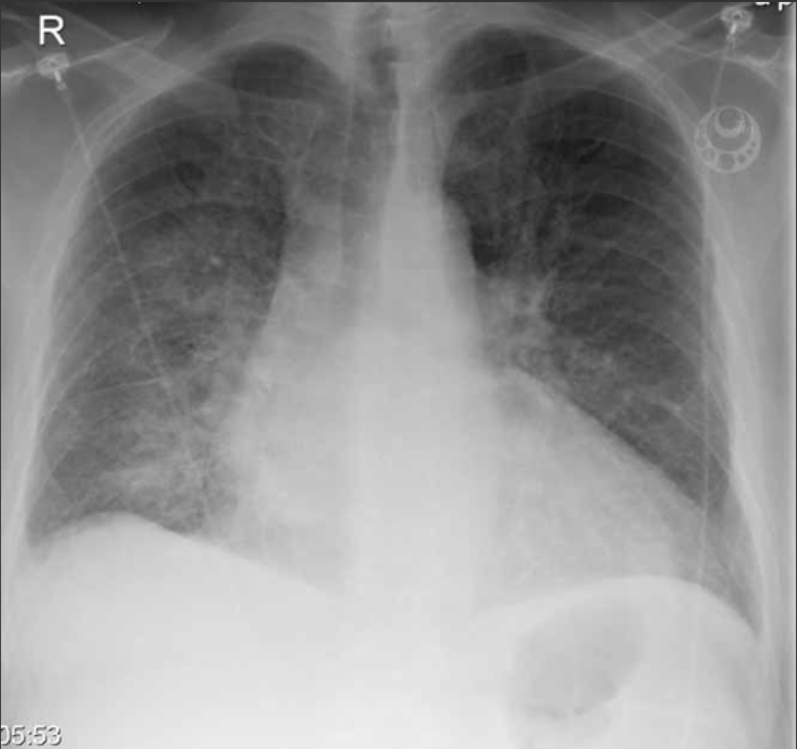

• (Nedom njurartärnivå finns ett 10 cm långt) bukaortaneurysm med en vidd av drygt 6.5 cm.